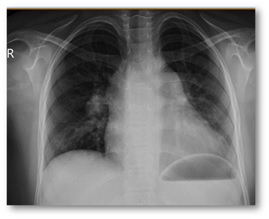

General

appearance: ill, pallor, Respiratory distress

Vital

sign: RR: 35/min, BP: 95/50 mmHg, T: 37, HR: 160/min, SpO2

at room air: 82%

shallow breathing, Inspiratory fine crackles in base of lungs

Cardiology consult: ECG: RVH, Echocardiography: RVH, Pulmonary

Atrial Pressure= 70 mmHg

Disease process:

She was admitted to pulmonology

ward: treatment for Pulmonary Atrial Hypertension (PAH) and right heart failure

was started.

تشخيص شما چيست؟